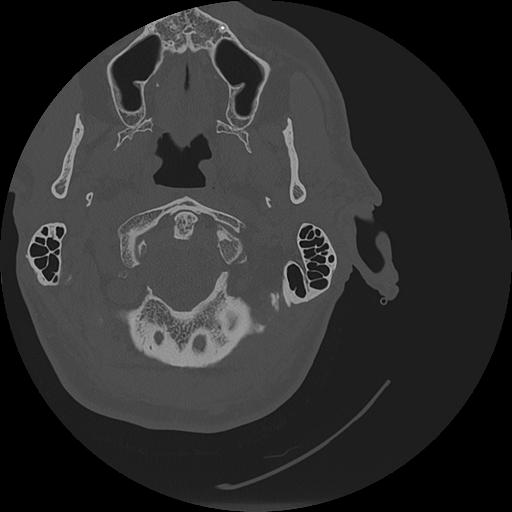

7 HUESO,,Vol,0.5,HUESO,,